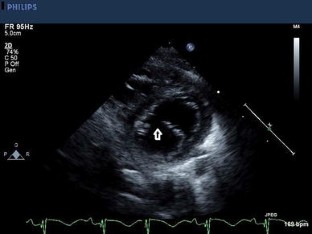

Fig. 1